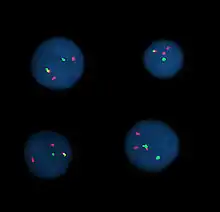

Interphase cells positive for a t(9;22) rearrangement

Fluorescence in situ hybridization (FISH) refers to using fluorescently labeled probe to hybridize to cytogenetic cell preparations.

Analysis

Analysis of FISH specimens is done by fluorescence microscopy by a clinical laboratory specialist in cytogenetics. For oncology, generally, a large number of interphase cells are scored in order to rule out low-level residual disease, generally between 200 and 1,000 cells are counted and scored. For congenital problems usually 20 metaphase cells are scored.